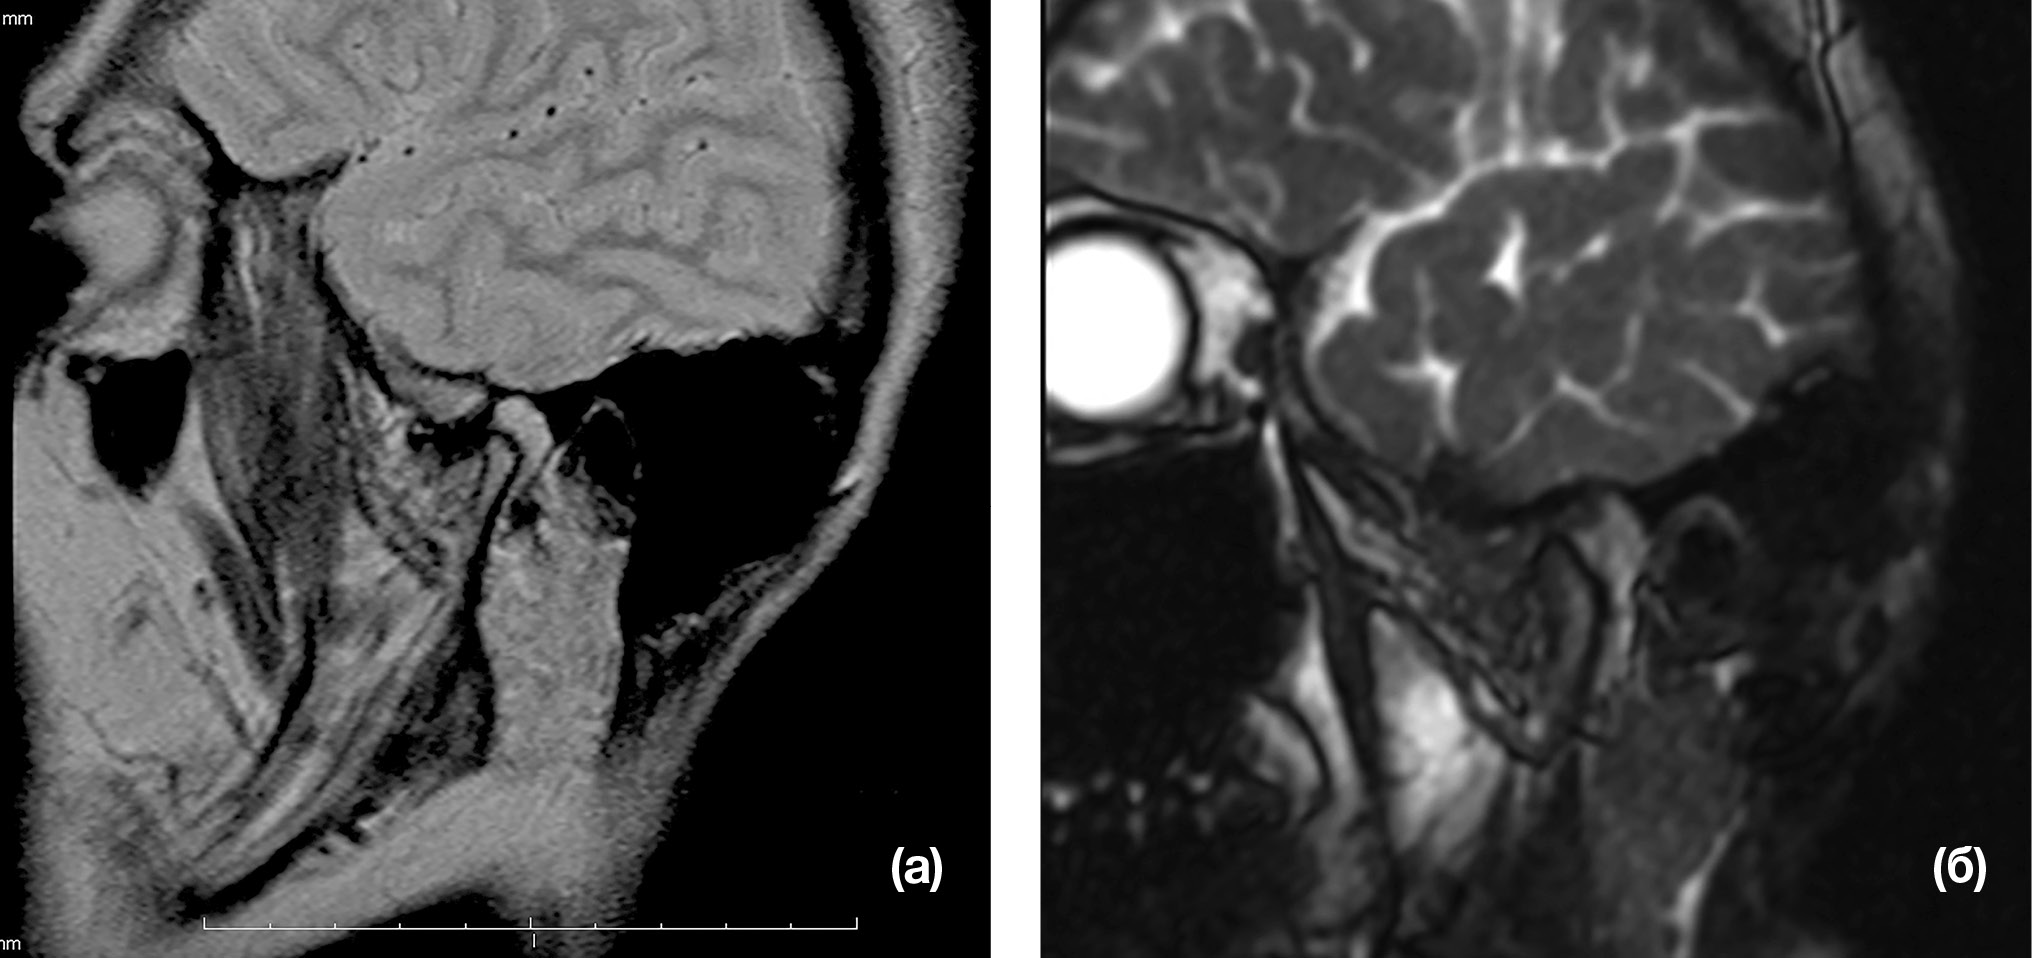

В 1-й группе боль при открывании рта постепенно уменьшалась и через 1 мес лечения полностью исчезла у всех пациентов. Полное восстановление функции ВНЧС происходило в течение 6 мес. При контрольной МРТ в сроки от 1 до 6 мес у 64,5% пациентов наблюдалось полное вправление суставного диска, у 35,5% вправление суставного диска было неполным, хотя он и не препятствовал открыванию рта (Рис. 1).

Рис. 1. Магнитно-резонансная томограмма височно-нижнечелюстного сустава с невправляемым смещением суставного диска: до (а) и после (б) лечения

Примечание. (а) — переднее (кпереди от головки нижней челюсти) положение суставного диска; (б) — верхнее (над головкой нижней челюсти) положение суставного диска.